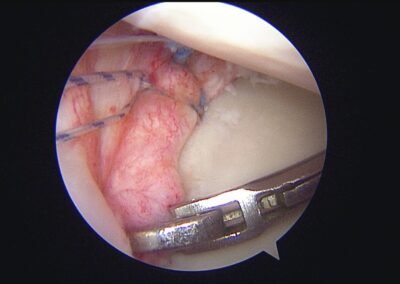

GalleryShoulder rotator cuff repair Meniscus root repair Meniscus repair Bankart repair for recurrent shoulder dislocation ACL reconstruction Machines Instruments